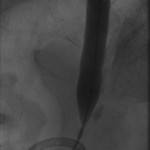

Access was gained from the back into a dilated posterior calyx of each kidney and secured with a sheath. Antegrade pyelogram on each side revealed marked ureteral and calyceal dilation due to complete obstruction of the distal ureter. A wire was advanced into the urinary bladder past the obstruction, which was dilated with a non-compliant balloon when it resisted the deployment of a nephroureteral stent. The stent was successfully deployed after the balloon dilation.

If obstructions are easy to cross, internal ureteral stents may be placed across them, with one end of the stent in the renal pelvis and the other in the urinary bladder. The stents should be changed periodically through the urethra by urologists or interventional radiologists. Sometimes, as in the patient whose images are displayed above, the obstruction must be predilated to permit insertion of the ureteral stents. Alternatively, a drainage catheter called a nephrostomy catheter can be deployed into the renal pelvis to drain urine into a bag attached to it without crossing the obstruction.